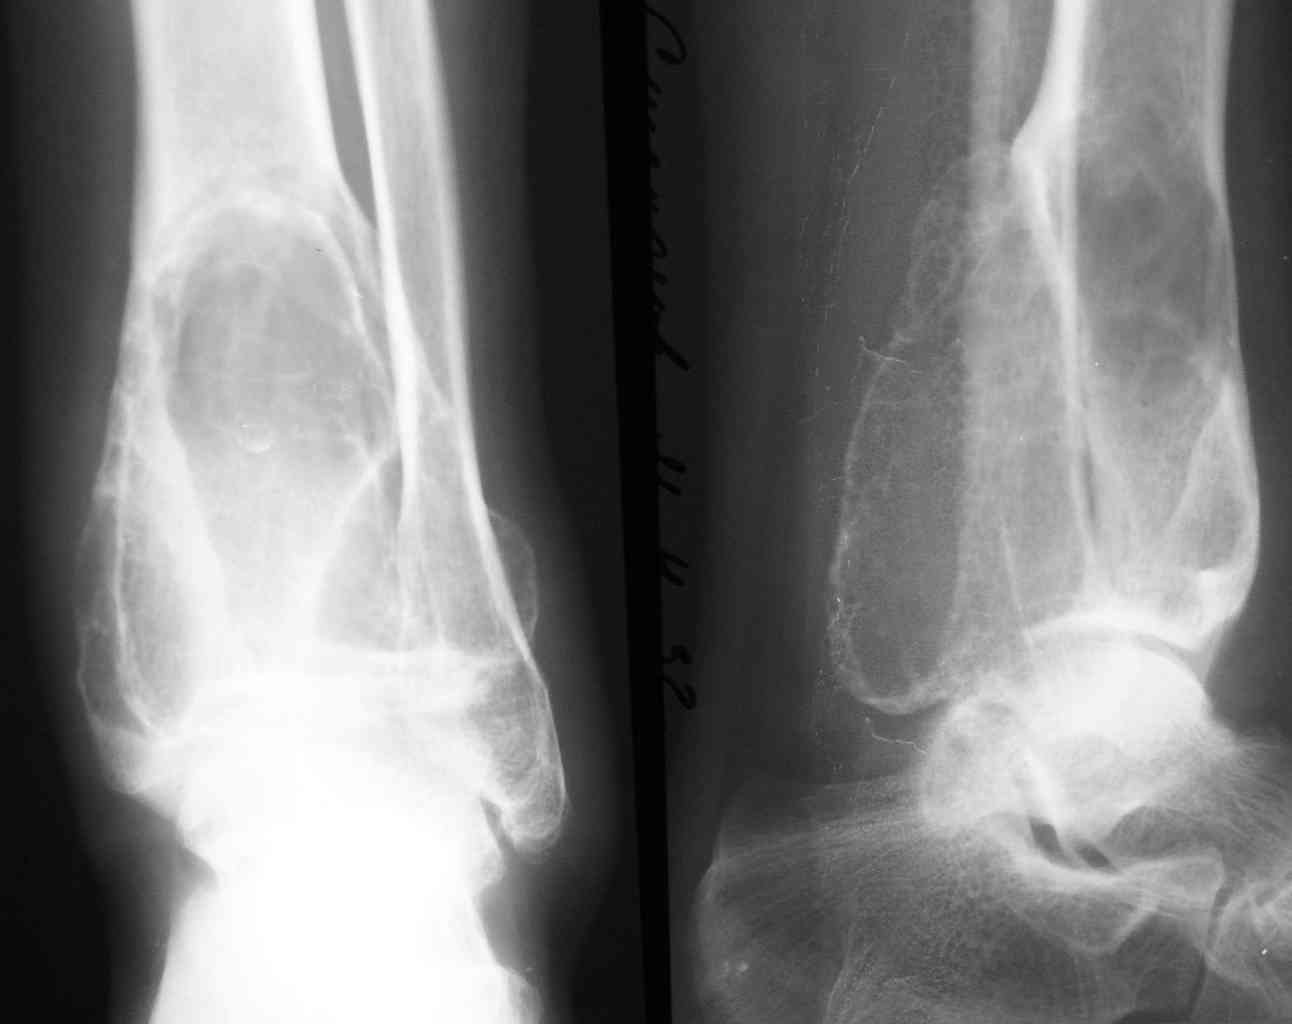

2-Пациент С.,32 лет,аневризмальная костная киста левой большеберцовой кости (Рис. 3,4), проходит лечение.